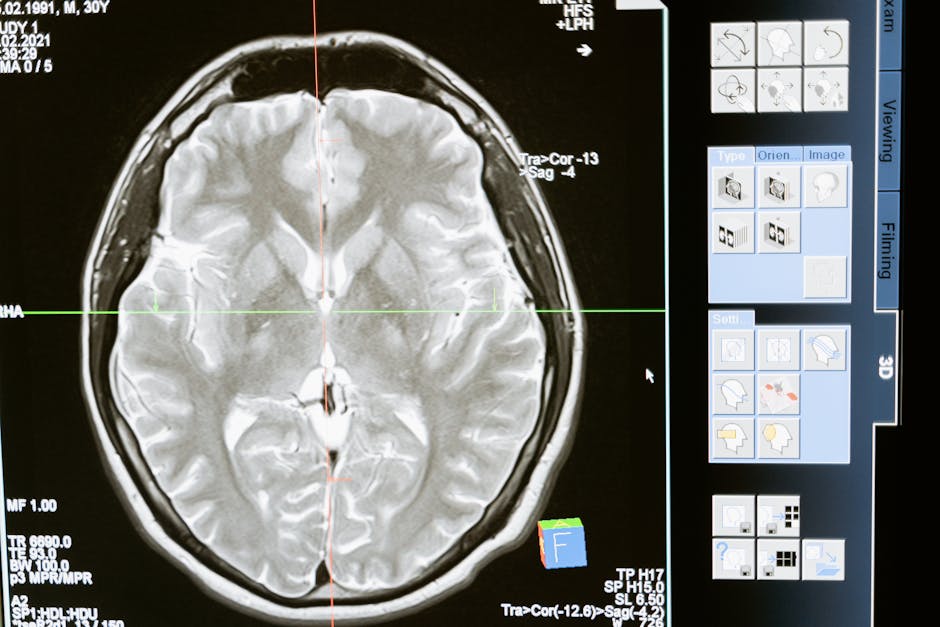

Chronic pain is a debilitating condition that affects millions of people worldwide, with approximately 50 million adults in the United States alone suffering from the condition. Despite its prevalence, the underlying mechanisms of chronic pain have long been poorly understood, leaving patients with limited treatment options. However, a recent breakthrough in research may have uncovered the brain’s switch for chronic pain, a discovery that could potentially revolutionize the way we approach pain management. Deep within the brain, scientists have identified a hidden region that acts as a command center, dictating whether pain signals should be silenced or allowed to persist.

The discovery of the brain’s switch for chronic pain is a significant one, and it comes at a time when the need for effective pain management solutions has never been more pressing. With the opioid crisis continuing to ravage communities across the globe, the search for alternative treatments has become increasingly urgent. The caudal granular insular cortex (CGIC), a small, little-known region of the brain, has been found to play a crucial role in the development and maintenance of chronic pain. By uncovering the mechanisms by which the CGIC operates, researchers hope to develop new, targeted therapies that can provide relief to those suffering from this debilitating condition.

Researchers have made significant strides in recent years in understanding the complex mechanisms that underlie chronic pain. While acute pain serves as a vital warning system, alerting us to potential dangers and facilitating the healing process, chronic pain is a different story altogether. Rather than serving a useful purpose, chronic pain can be a crippling and relentless companion, disrupting every aspect of a person’s life. The CGIC has been found to be a key player in this process, acting as a switch that can either silence or amplify pain signals. In animal studies, shutting down this pathway has been shown to not only prevent chronic pain from forming but also to erase it once it has taken hold.